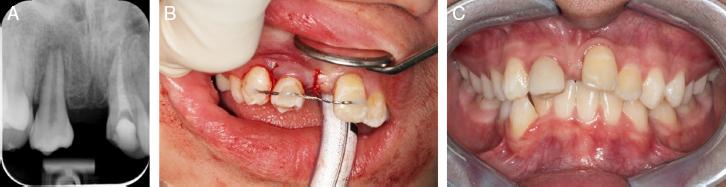

Prior to the extraction of the donor teeth (#35 and #45), full mucoperiosteal flap elevation and preparation of the recipient beds at #12 and #21 were performed to minimise the exposure time of the donor teeth outside of the mouth. The thin overlying labial bone fractured off during the removal of the ankylosed #21. The lower left and right second premolars were exposed, atraumatically extracted with forceps and placed into the newly created recipient sockets 2 mm below the occlusal plane and stabilised with a passive and flexible wire splint (Figure 9A-C). Careful handling of the donor teeth was ensured to avoid disturbances of Hertwig’s root sheath. Two weeks later, spontaneous eruption of the transplanted teeth had occurred, and the palatal surfaces were trimmed to reduce occlusal interferences.

(A) Periapical radiograph taken 1 week post-autotransplantation; teeth #35 and #45 secured with a flexible wire splint. (B) Lower second premolars transplanted into the anterior maxilla region. (C) Composite build-up 2 months post-autrotransplantation.